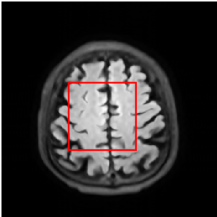

Figure 5 provides the qualitative comparison of the various methods on the four datasets at a scale of 4. The top, second, third, and bottom rows are the SR results under the FastMRI, clinical brain, clinical tumor and clinical pelvic datasets, respectively. The red boxes indicate the zoom-in region of complicated anatomical structures along with their corresponding error maps. Note that the brighter textures in the error maps, the lower the quality of the reconstructed images. As can be seen, compared to methods based on Transformers and CNNs, diffusion-based methods like DisC-Diff and DiffMSR (Ours) are capable of reconstructing high-realistic images with promising reconstruction metric scores (PSNR and SSIM). Nevertheless, while DisC-Diff can reconstruct high-precision MR images, it does not preserve the structure present in the original HR images, introducing some additional information that can affect medical diagnosis. In contrast, our method combines DM and PLWformer, which can preserve the original image’s structure while restoring high-frequency information.